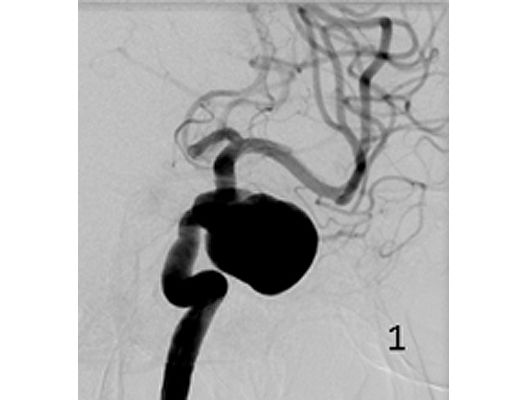

Angiographie: Behandlung von Aneurysmen

Behandlung von Aneurysmen

Aneurysmen an der Gefäßen des Gehirns können in vielen Fällen minimalinvasiv durch einen Zugang durch das Gefäßsystem, zumeist von der Leiste aus behandelt werden (sog. Endovaskuläre Therapie). Dabei gibt es z.B. die Möglichkeit ein Aneurysma durch Einbringung von Platinspiralen zu verschließen (sog. Coiling). Auch für komplexe Aneurysmen stehen inzwischen verschiedene endovaskuläre Methoden zur Verfügung.

Das Beispiel zeigt die angiographischen Bilder einer Patientin, bei der es zu einer Sehstörung gekommen war. Die Ursache war ein großes Aneurysma der Halsschlagader an der Schädelbasis (Bild 1). Bild 2 zeigt die Lage des Aneurysmas hinter dem Auge. Durch den Druck des Aneurysmas auf den Sehnerv war es zu der Sehstörung gekommen. Die Patientin wurde mit einer speziellen Gefäßprothese versorgt, welche über eine Punktion der Leistenarterie in die Halsschlagader eingesetzt wurde (Bild 3). Bei der Kontrolle nach 6 Monaten zeigte sich ein vollständiger Verschluss des Aneurysmas (Bild 4). Die Sehstörung hatte sich vollständig zurückgebildet.